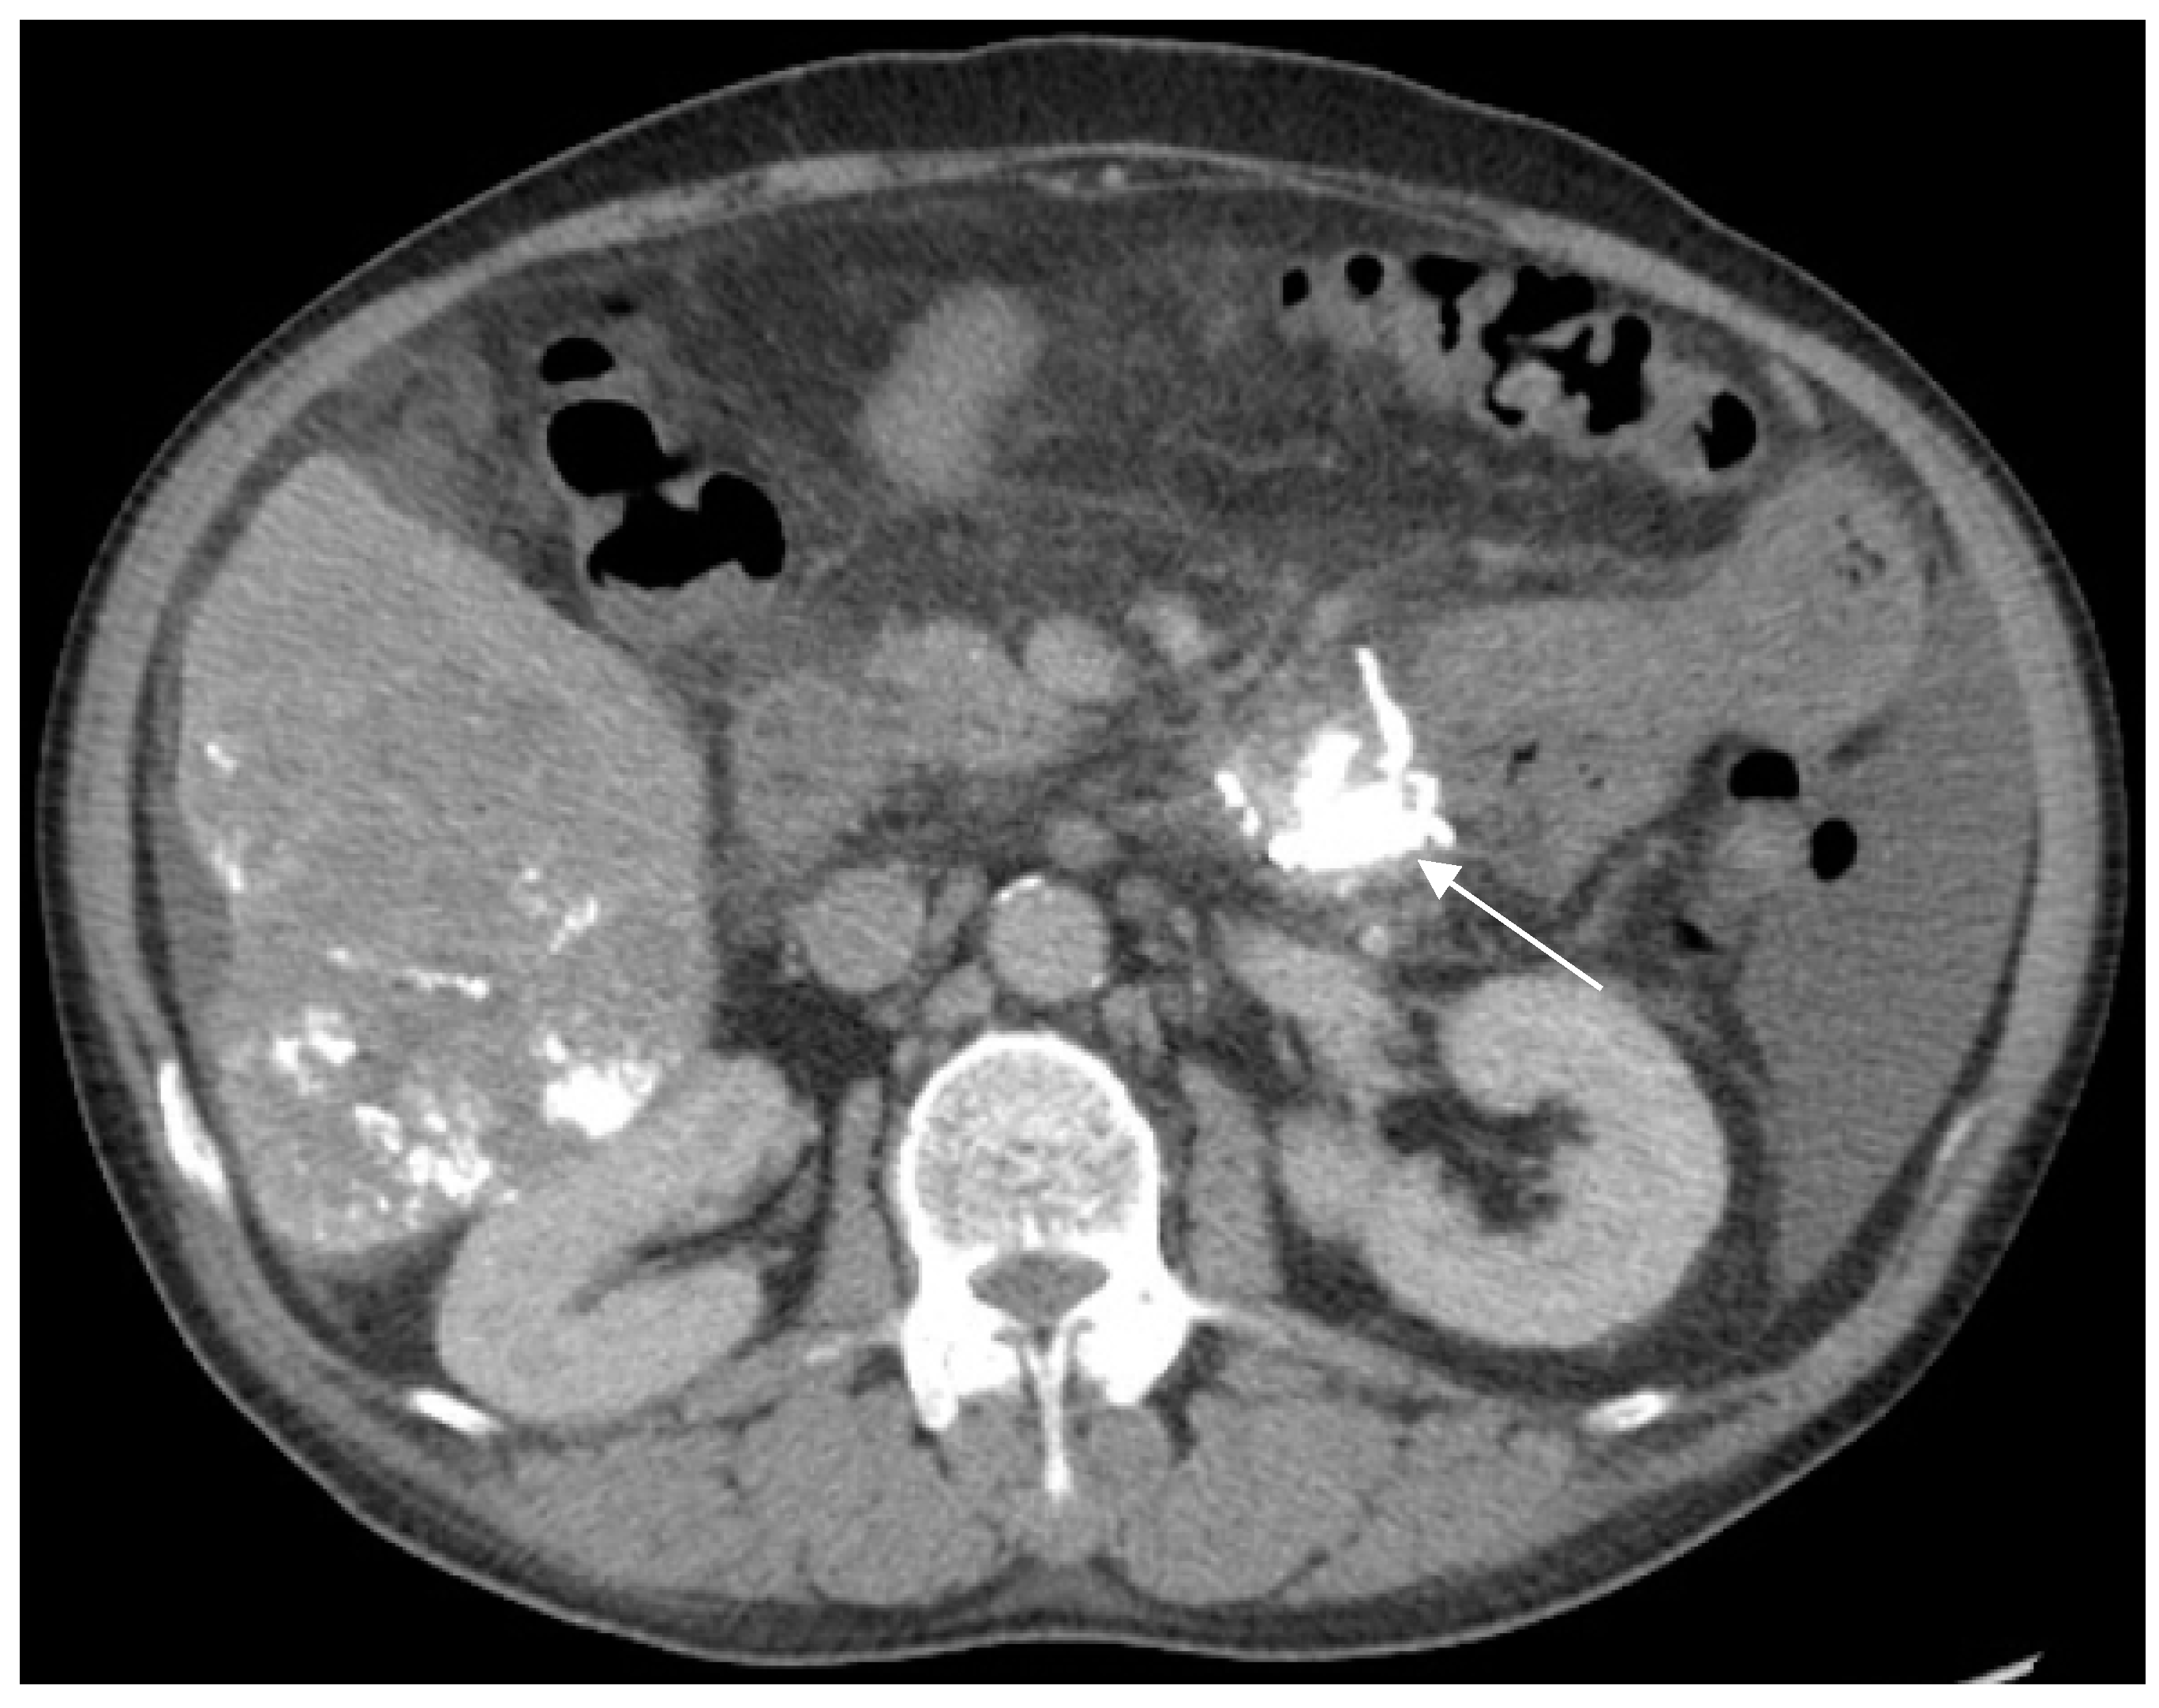

2. Case Report